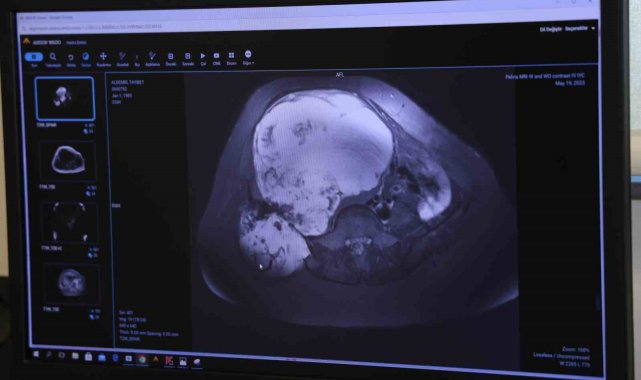

Mardin'de doğum yaptığı sırada sağ leğen kemiğinde tümör tespit edilen ve doktorların 'Ya bacağın kesilir ya da ölürsün' diyerek ameliyat etmekten çekindiği kadın, Adana'da 6 saat süren 'Pelvik rezeksiyon' ameliyatıyla yeniden sağlığına kavuştu.Mardin'de yaşayan 35 yaşındaki Tayyibet Aldemir'e, 3 sene önce 3. çocuğunun doğumu sırasında sağ leğen kemiğinde tümör teşhisi konuldu. Bunun üzerine doğumdan sonra Diyarbakır'a yönlendirilen Aldemir, orada da ameliyat edilemeyince İstanbul'a sevk edildi. İstanbul'da da doktorların 'Ya bacağın kesilir ya da ölürsün' demesi üzerine genç kadın ameliyat olmaktan vazgeçti.Yürüyememeye başladıGün geçtikçe yürüme kabiliyetini de kaybeden Aldemir, hem yeni doğan bebeğine hem de diğer çocuklarına artık bakamamaya başladı. 1.5 yıl boyunca acı çeken Aldemir, kızının tedavisi için Adana Şehir Eğitim ve Araştırma Hastanesi'ne geldi.Ameliyat olmaya karar verdiBurada Ortopedi ve Travmatoloji Kliniği'nde görevli Prof. Dr. Ahmet Kapukaya'ya başvuran Aldemir, yapılan tetkikler sonucu doktorunun da yönlendirmesiyle ameliyat olmaya karar verdi. Türkiye'de nadir yapılan ve 6 saat süren 'Pelvik rezeksiyon' ameliyatıyla genç kadının leğen kemiğindeki tümör temizlendi.Artık evlatlarına bakabiliyorAmeliyattan sonra sağlığına kavuşan Tayyibet Aldemir artık kimseden yardım almadan hem 3 çocuğuna hem de evine bakabiliyor."Hastanemizin alt yapısı ameliyatlar için müsait"İhlas Haber Ajansı'na konuşan Ortopedi ve Travmatoloji Uzmanı Prof. Dr. Ahmet Kapukaya, "Hastamız bize geldiğinde tümörü çok ilerlemişti. Ameliyat olması halinde yüzde 98 bacak kaybı, yüzde 95'de ölüm riski var denilmişti. Ancak Adana Şehir Eğitim ve Araştırma Hastanemizin alt yapısı bu tür ameliyatları yapmaya çok müsait. Bizde hastamıza riskleri anlattık ve ekip halinde bu ameliyatı gerçekleştirdik. Leğen kemiğini bölgeden çıkarttık, tümörü temizledik ve vücuttan alınan diğer kemiklerle o bölgede yeni bir leğen kemiği oluşması için kaynamaya bıraktık" diye konuştu."Sağlığıma kavuştum"Ameliyattan önce çok zor günler geçirdiğini anlatan Tayyibet Aldemir, "Çocuklarıma dahi bakamıyordum, komşular, akrabalar evlatlarıma bakıyordu. Ameliyattan sonra çok rahatladım. Şuanda çok iyiyim. Türkiye'de birçok özel ve devlet hastanesine gittim ancak bir türlü ameliyat olamadım. Adana'da ameliyat oldum ve sağlığıma kavuştum" dedi.